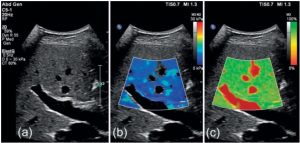

Еластографія може візуалізуватися як кольорова карта (еластограма) або числові значення (наприклад, в кПа) — чим вища жорсткість, то вища ймовірність вираженого фіброзу.